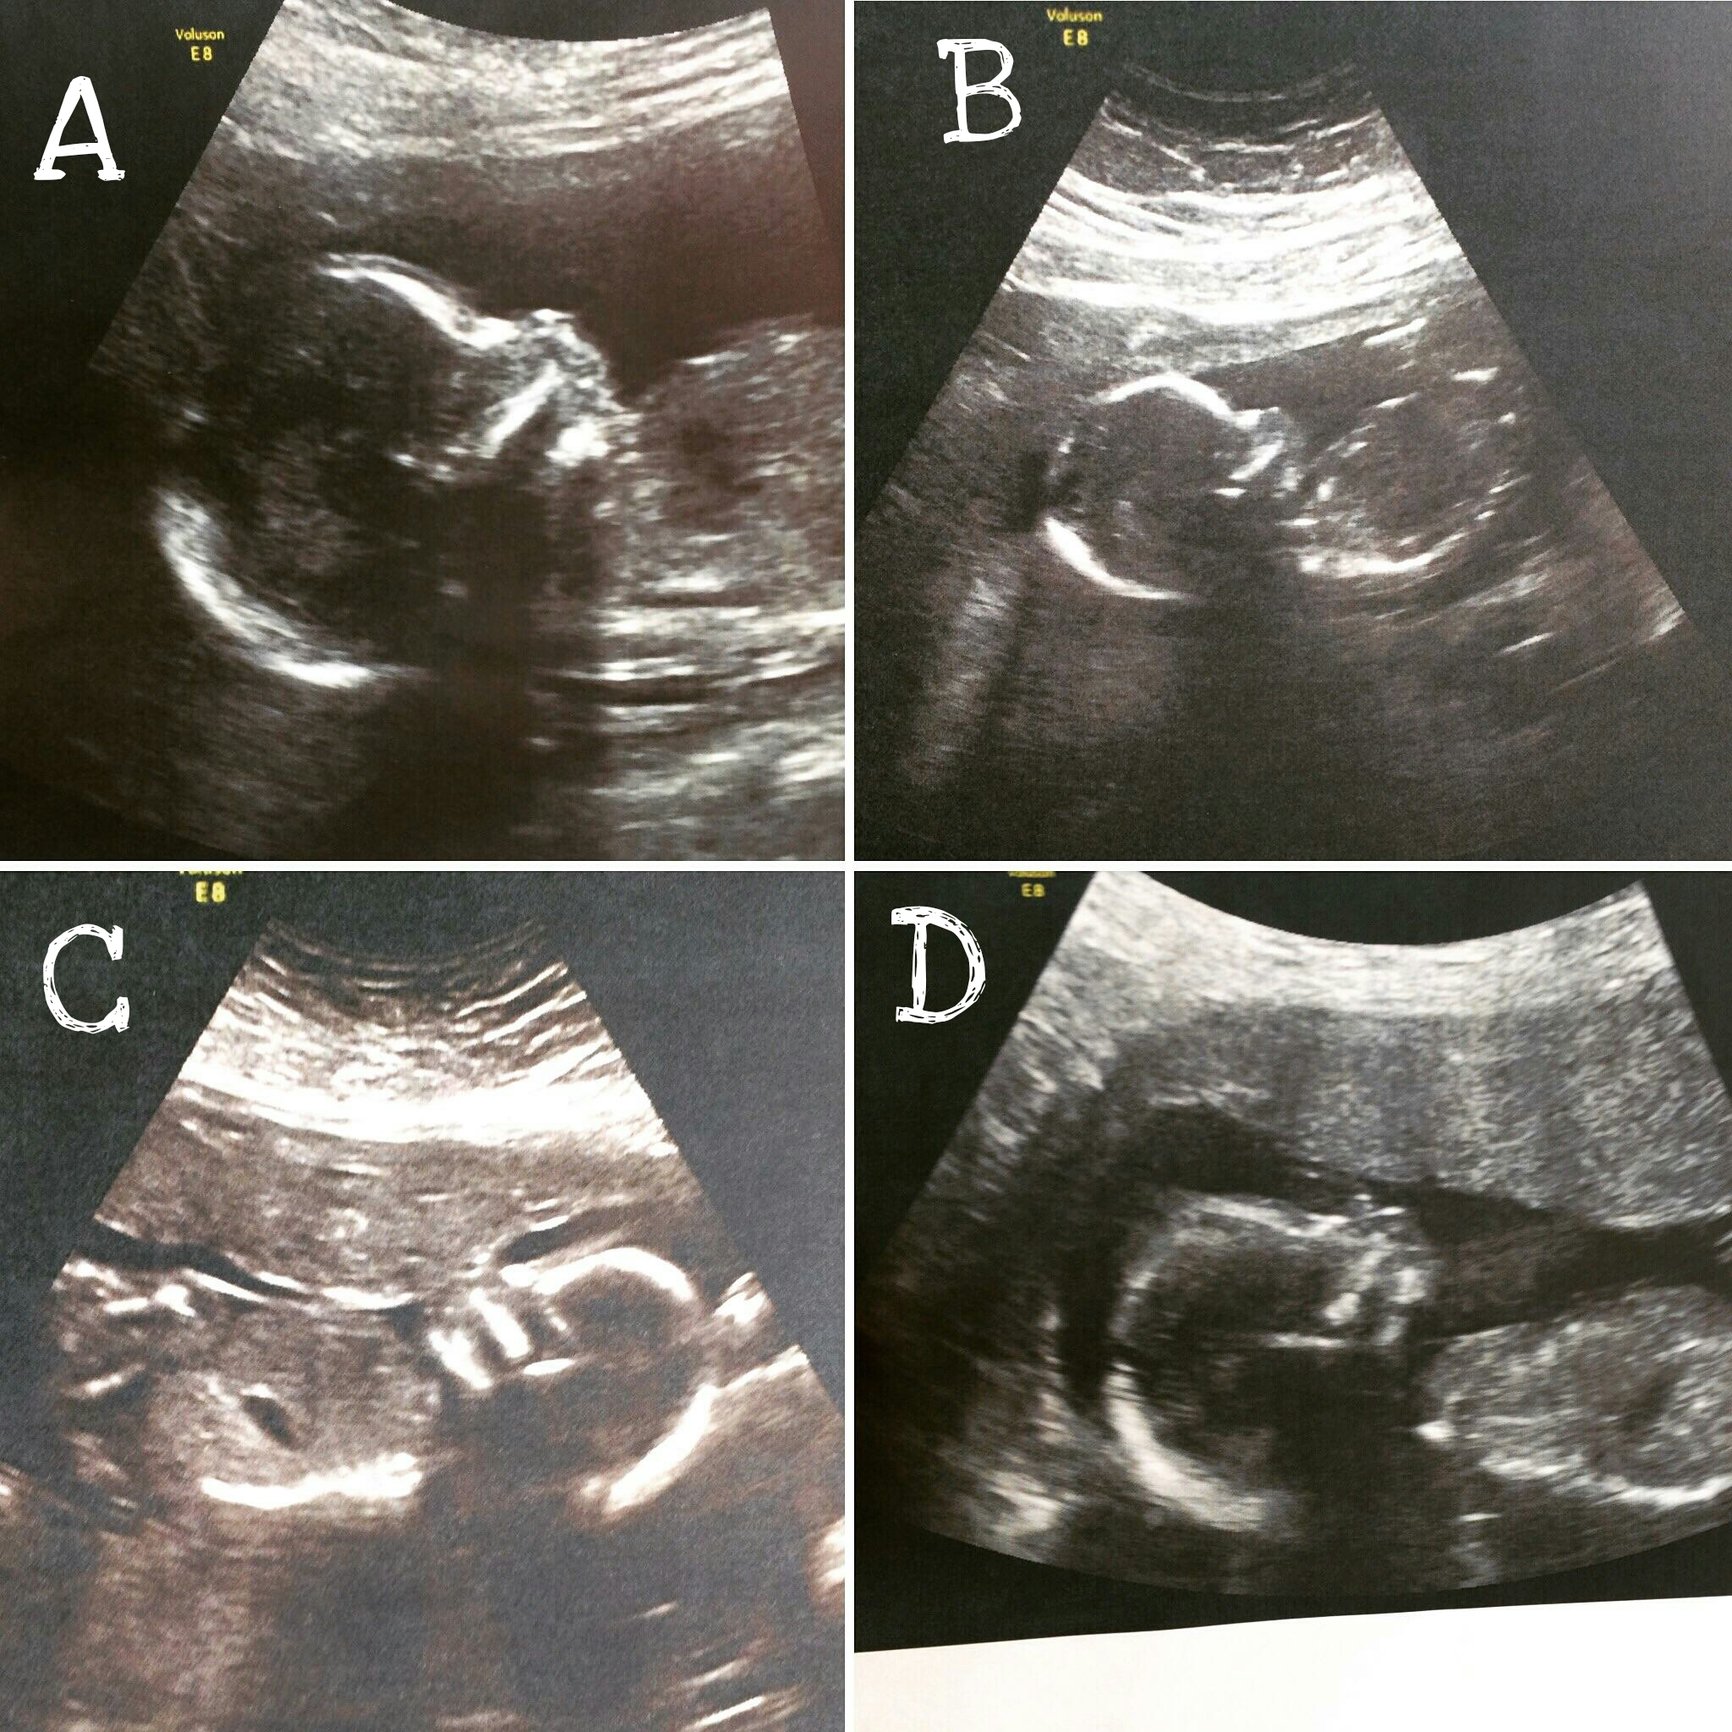

As I posted in the weekly multiples post today we were having our anatomy scan for the quads. The anatomy scan took about 1 1/2 hours and the babies cooperated very well! everything looks excellent but we do need to go back in two weeks because we couldn't get all of the facial shots needed on all babies due to their position. we were able to get excellent clear images of the their hearts and other organs which all look perfect. We were also able to determine the genders! Baby A is boy, baby B is a girl, Baby C is a girl and Baby D is a Boy! although this still does not seem real to me I am very relieved to know that all are healthy and growing and so very thankful. I hope you all enjoy these updates just as much as I do!

As I posted in the weekly multiples post today we were having our anatomy scan for the quads. The anatomy scan took about 1 1/2 hours and the babies cooperated very well! everything looks excellent but we do need to go back in two weeks because we couldn't get all of the facial shots needed on all babies due to their position. we were able to get excellent clear images of the their hearts and other organs which all look perfect. We were also able to determine the genders! Baby A is boy, baby B is a girl, Baby C is a girl and Baby D is a Boy! although this still does not seem real to me I am very relieved to know that all are healthy and growing and so very thankful. I hope you all enjoy these updates just as much as I do!